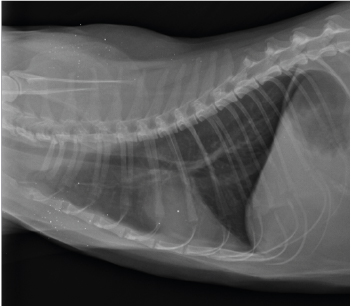

Utilisation de la théophylline reconditionnée lors d’asthme chez un chat Anamnèse et commémoratifs Oslo est un chat européen mâle castré de 1 an, qui est